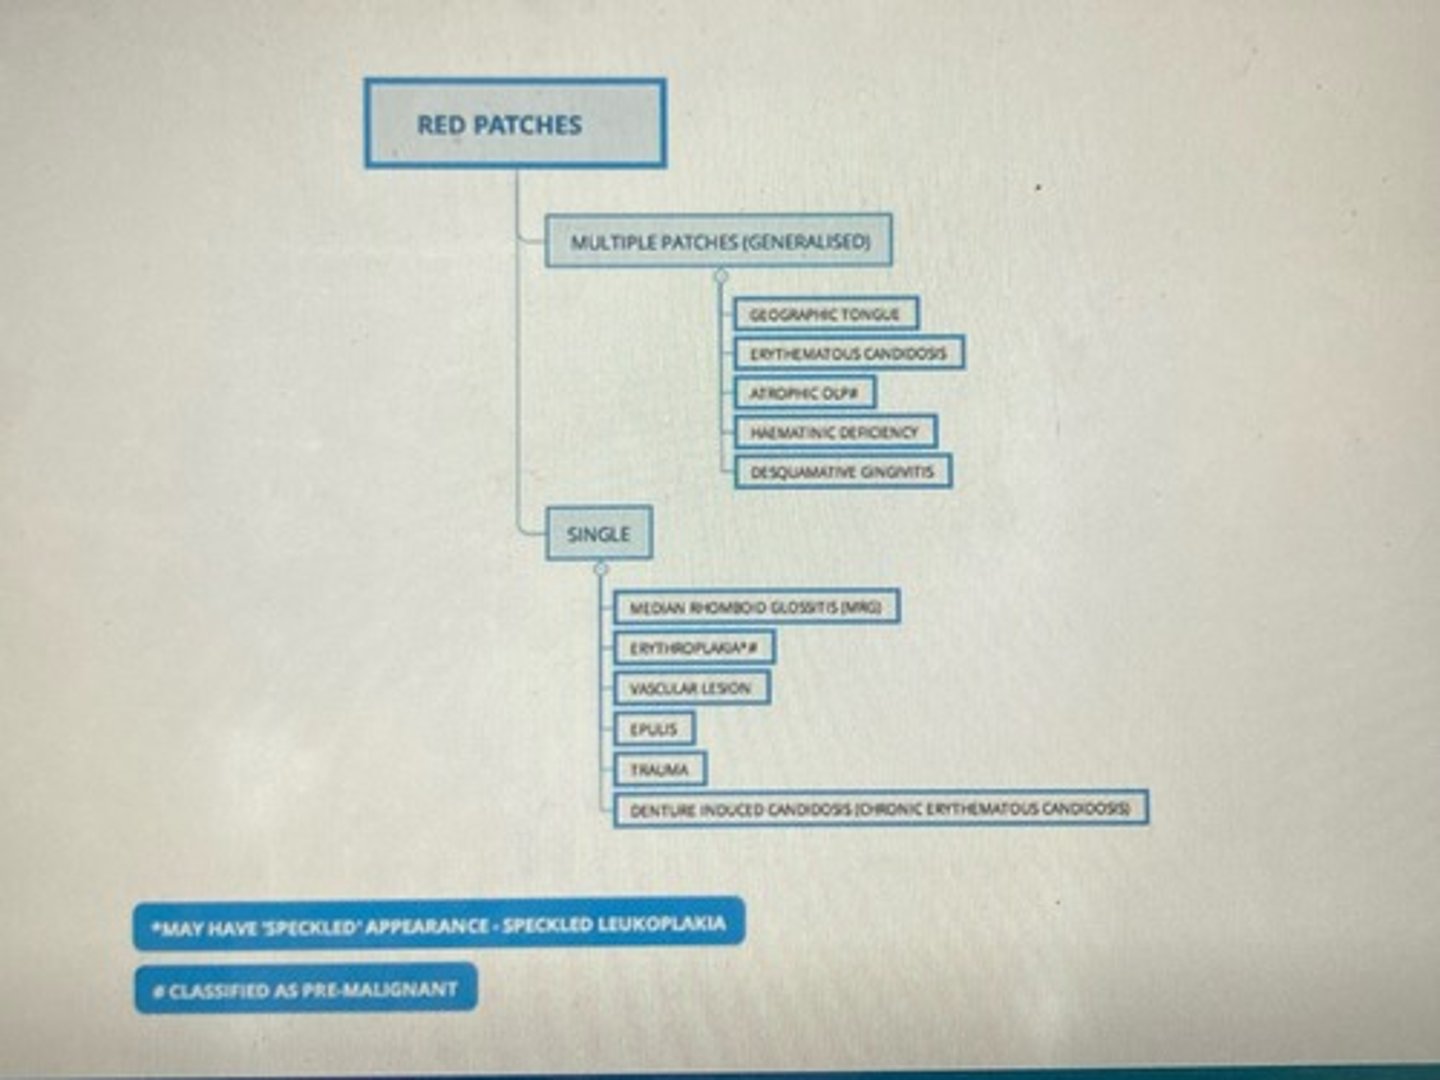

Red patches: multiple & single

geographic tongue/ benign migratory glossitis/ erythema migrans

diagnosis made on clinical app

What do you think the diagnosis is?

doesn't need referring to OM unless uncertain of diagnosis or tongue is persistently sore

in this case, pt would need blood tests to investigate for anaemia & haematinic deficiencies

Would you refer the patient and if so why?

reassure pt this is not an infectious condition

common benign condition & can run in families

The patient is worried about sharing cutlery with his family, what would you advise him?

- glossitis (anaemia & harmatinic deficiencies)

- mucositis (radio/chemo)

- mucosal disease (eg LP)

What are some other causes of smooth tongue?

chronic erythematous candidosis

What is the likely diagnosis?

LP or immunobullous condition (Pemphigus & Pemphigoid) can also cause desquamative gingivitis

What is the likely diagnosis?

Erythroplakia (potentially malignant lesion)

What is the likely diagnosis?